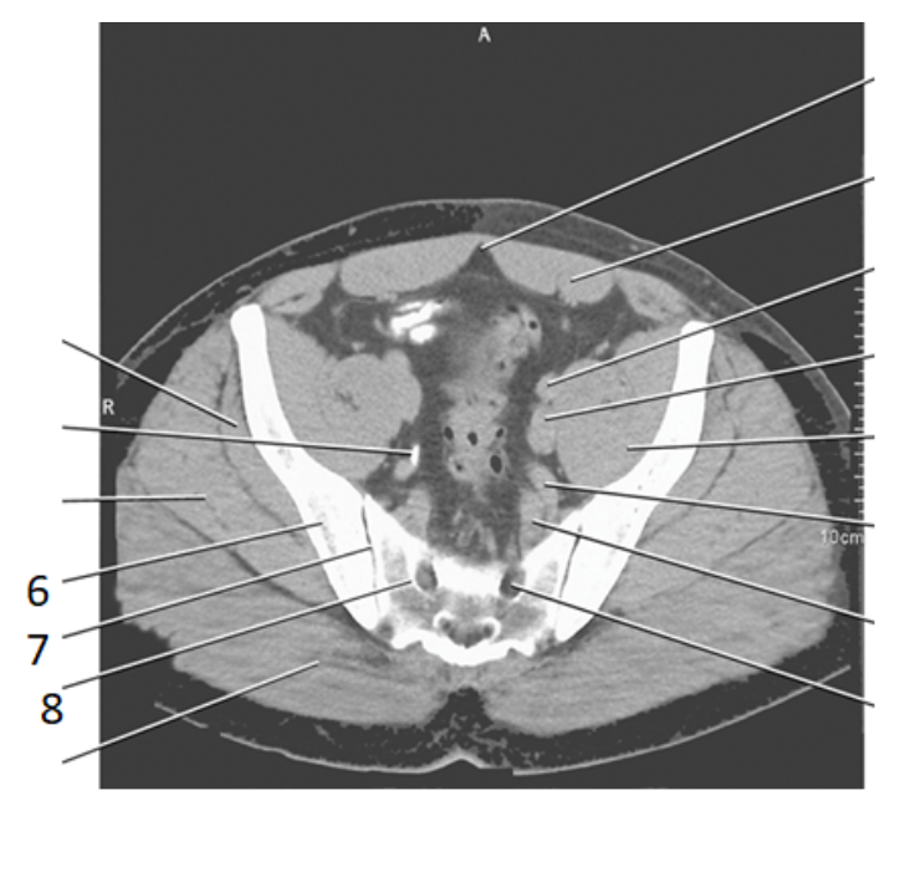

6

ilium

7

SI joint

8

psoas

9

sacram foramen

2

aorta